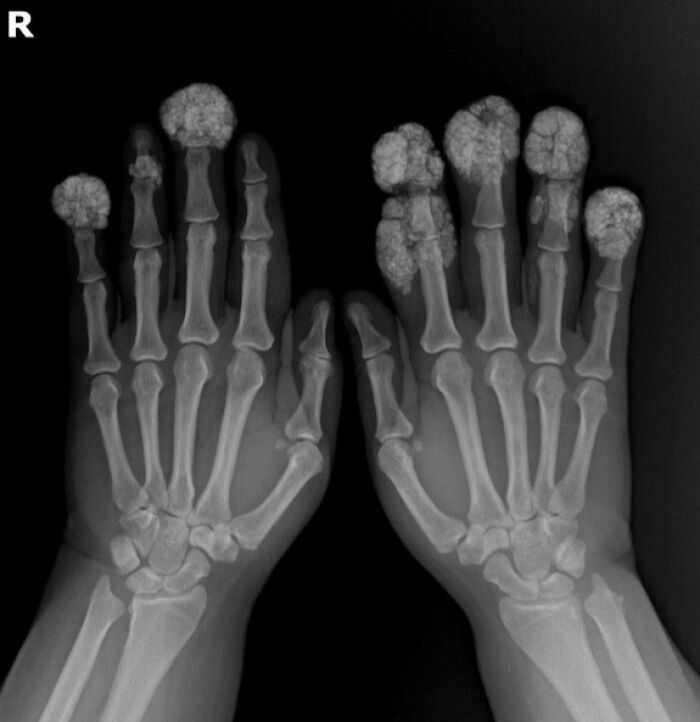

X-Ray Of A Hand With Advanced Rheumatoid Arthiritis